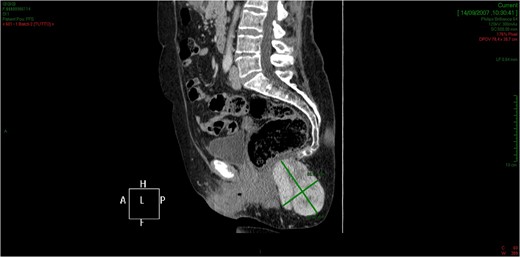

CT showed an hyperintense and inhomogeneous solid lesion taking up the right ischiorectal fossa (maximum diameter of about 10 cm), extended cranially until impressing the wall of the rectal ampulla, with no apparent infiltration (Figs 2 and 3). The lesion presented an intense contrast enhancement, sign of a rich vascularization (Fig. 4).

The tridimensional reconstruction shows the rich vascularization of the neoplasm.